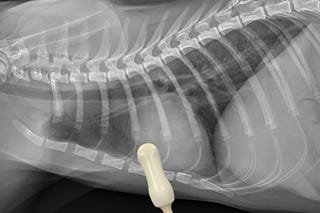

Empleo de fluoroscopia en colapso traqueal

Ejemplo gráfico de esta herramienta diagnóstica.

Fluoroscopia en perros con colapso traqueal

Repasamos esta modalidad diagnóstica en perros con colapso traqueal.